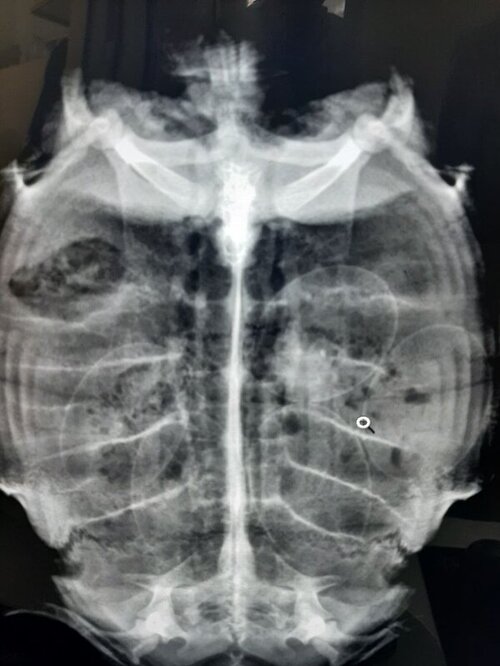

katerina.fotiadi Ваше имя: много Локация: узбекистан .коканд Опубликовано: 22 февраля 2022 Автор Опубликовано: 22 февраля 2022 9 часов назад, moth сказал: @katerina.fotiadi врач ответила 5 дней делать кальций, дальше смотреть на состояние черепахи. Если кладки так и не будет - я Вам посчитаю окситоцин, но это будет под Вашу ответственность. Сегодння звонила в Ташкентский зоопарк.сделали рентген яица с прошлого года остались .сейчас жду ответа от ветеринара с зоопарка если она скажет везти оперировать то поедем